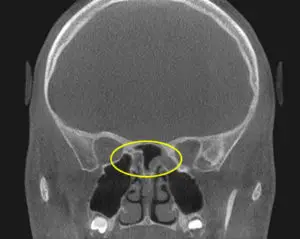

Physical Exam: Clinical and physical exam revealed a component of pressure overlying the frontal(forehead) region. Further, the child says there is a “behind the eye” pressure sensation as well. A nasal endoscopy was performed revealing no evidence of nasal polyps. There was, however, some swelling in the region of normal sinus drainage – likely preventing normal drainage and causing a build-up of pressure. An in-office CT Sinus was then performed revealing evidence of trapped sinus secretions at both the frontal (PreOp CT Scan 1) and sphenoid sinus (PreOp CT Scan 2). This resulted in an accurate diagnosis of headache secondary to chronic frontal and sphenoid sinusitis.

PreOp CT Scan: (2/2016)